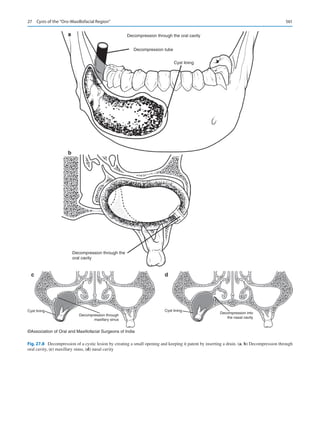

2.	 Management of oral cancer.

3.	 Management of craniofacial anomalies.

His views suggested that the advent of seatbelts, airbags,

and safer road conditions in most countries is diminishing

our total volume of trauma. Further, patterns of wars have

changed from the bayonets of World War I to drone-­

controlled annihilation that ensures death! While bar fights

and interpersonal violence continue to create left-sided ZMC

and mandibular fractures, the world of facial trauma is most

certainly changing.

He recognized examples of how personalized medicine is

influencing the care of cancer patients. With our ability to